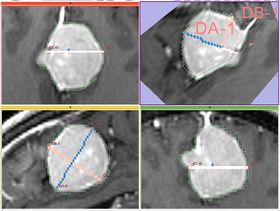

- Implementation details The module implements the following algorithm for calculating the dimensions of the label. First, the area of the label slice is computed in all the slices of the image that are passing through the label. This is done for the three orthogonal directions of the image. The largest area slice is found. The largest diameter (DA) is estimated by finding the two most distant points on the contour of the label cross-section. The second diameter (DB) is found by finding the two most distant points on the contour that lie on the line perpendicular to the first diameter. The third diameter (DC) is estimated by calculating the two points of intersection between the line perpendicular to the plane formed by DA and DBpassing through the point of their intersection, and the contour of the analyzed label.